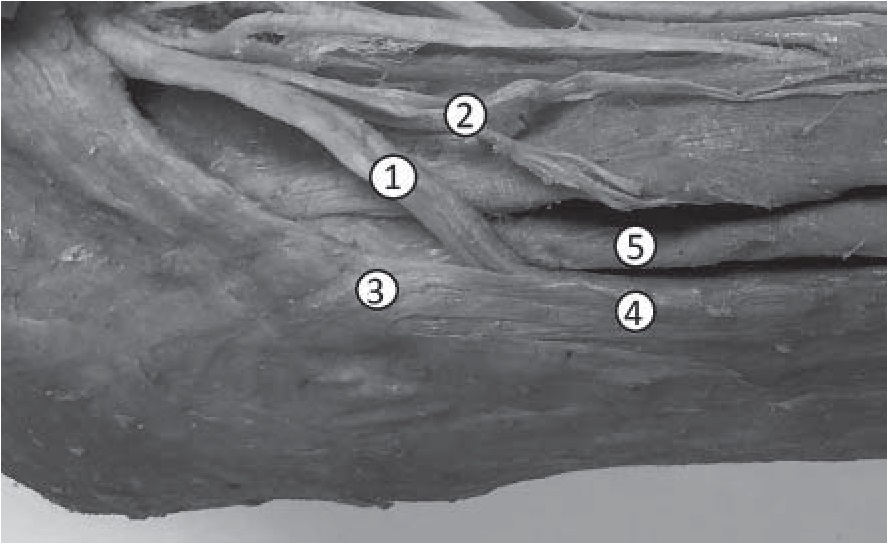

Результаты и их обсуждение. При изучении уровня формирования общего малоберцового нерва выявлено, что в 24 (33,3%) случаях отмечается «высокий» уровень деления седалищного нерва на конечные ветви. При таком варианте ствол общего малоберцового нерва формируется на уровне верхней трети бедра и на всем протяжении бедра располагается параллельно большеберцовому нерву. Угол расхождения общего малоберцового и большеберцового нервов составляет 6,2±3,2о (рис. 1).

Рис. 1. Вариант «высокого» формирования общего малоберцового нерва: 1 – ствол седалищного нерва; 2 – большеберцовый нерв; 3 – общий малоберцовый нерв

При таком варианте формирования отмечено, что стволы большеберцового и общего малоберцового нерва, располагаясь параллельно, каждый в своей эпиневральной оболочке, имели в 20 (83,3%) случаях из 24 один или несколько анастомозов между собой, что соответствует данным А.С. Вишневского, А.Н. Максименкова [1]. При «высоком» уровне формирования первая ветвь (латеральный кожный нерв икры) отходила в среднем на расстоянии 38,2±2,1 см от места деления седалищного нерва. Как правило, такой вариант формирования общего малоберцового нерва встречается при длине нижней конечности более 100 см. При этом диаметр нерва в области его формирования составлял 13,0±7,5 мм.